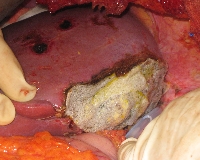

Πρόκειται για άνδρα ασθενή 58 ετών, ο οποίος υποβλήθηκε σε αξονική τομογραφία για επιγαστραλγία. Διαπιστώθηκε μάζα στην ουρά του παγκρέατος μεγέθους 5 εκατοστών, καθώς και πολλαπλές (περίπου 50) ηπατικές μεταστάσεις (εικόνες 1, 2). Βιοψία μίας από τις ηπατικές μάζες ανέδειξε νευροενδοκρινές καρκίνωμα καλής διαφοροποίησης. Ο ασθενής υποβλήθηκε σε ουραία παγκρεατεκτομή με σπληνεκτομή (εικόνα 3), αριστερή ηπατεκτομή μετά του 1ου τμήματος (εικόνα 4), τέσσερεις άτυπες δεξιές ηπατεκτομές και πολλαπλές κατευθυνόμενες (IOUS) εστιακές καταστροφές με μικροκύματα (εικόνα 5). Ογκομετρική αξονική την 7η μετεγχειρητική ημέρα ανέδειξε μείωση του μεταστατικού φορτίου σε ποσοστό > 90%. Κατόπιν, την 6η και 10η μετεγχειρητική εβδομάδα, ο ασθενής υποβλήθηκε σε διαδοχικούς υπερεκλεκτικούς (πρόσθιο και οπίσθιο) εμβολισμούς της δεξιάς ηπατικής αρτηρίας (εικόνα 6, απεικόνιση του πρόσθιου μετά από εμβολισμό του οπίσθιου τομεϊκού δεξιού αρτηριακού κλάδου). Οctreotide-scan τη 12η μετεγχειρητική εβδομάδα ανέδειξε απουσία ενεργών νευροενδοκρινών εστιών. Ο ασθενής λαμβάνει Sandostatin LAR εφ' όρου ζωής.